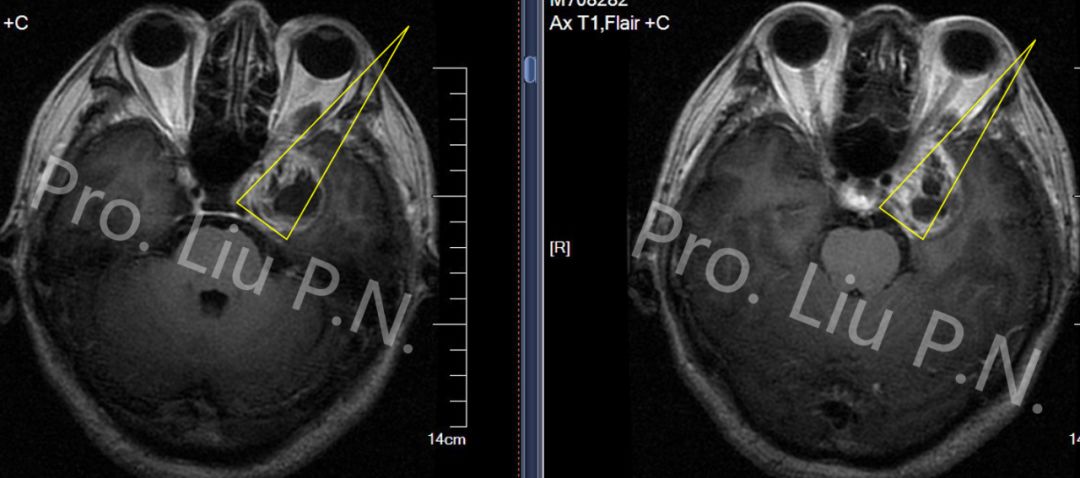

十、经筛-翼突入路手术案例

--左海绵窦神经鞘瘤

![]()